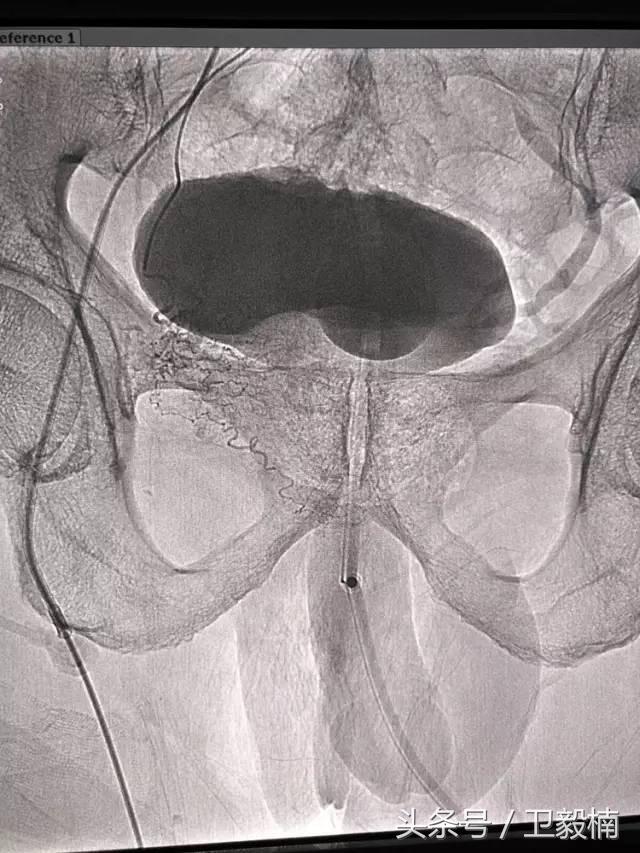

五、出血性疾病:鼻腔大出血、咯血、上消化道大出血、经皮肾镜术后出血、膀胱出血、产后出血等

2、经导管血管栓塞法(Transcatheter embolization)

经原血管造影的导管或特制的导管,将栓塞物送至靶血管内,一是治疗内出血如外伤性脏器出血、溃疡病、肿瘤或原因未明的脏器出血。另一是用栓塞法治疗肿瘤,因肿瘤循环部分或全部被栓塞物阻断,以达控制肿瘤之生长,或作为手术切除的一种治疗手段;亦可用于非手术脏器切除,例如注射栓塞物质于脾动脉分支内,即部分性脾栓塞,以治疗脾功亢进,同时不影响脾脏的免疫功能。

常用的栓塞物质如自体血凝块、明胶海绵、无水酒精、聚乙烯醇、液体硅酮、不锈钢圈、金属或塑料小球及中药白芨等。

(3)应用栓塞材料,钢圈,内支架治疗动脉瘤、AVM、动静脉瘘,血管性出血。